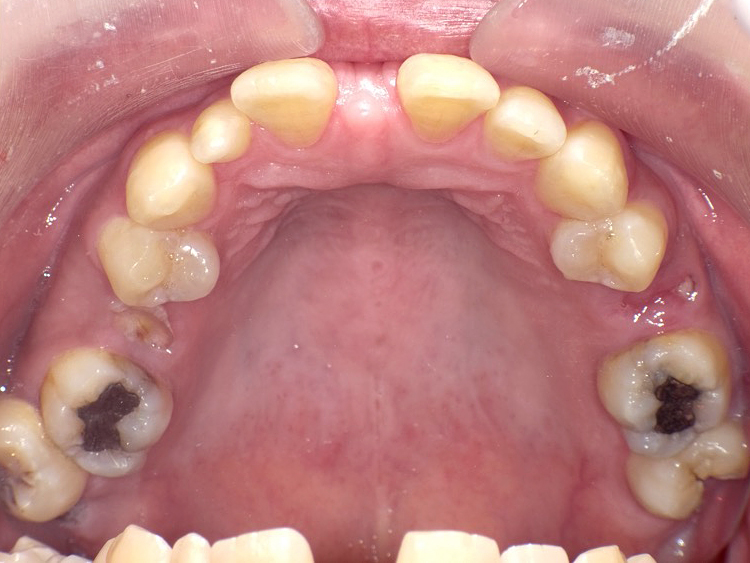

症例3

Before

After

| 主訴 | 上下の歯のガタガタを治したい |

|---|---|

| 年齢 | --- |

| 治療期間 | 約10ヶ月 |

| 治療内容 | インビザラインiGoで上下顎の治療。 狭まっていた歯並びを広げることで、 ガタガタに並んでいた歯を綺麗に並べた。 |

| 治療費 | ¥517,000(税込)+月額調整料 |

| 治療のリスク | 歯と歯の間を削ることでスペースを確保するので、 場合によっては歯が染みる症状が出ることがある。 |